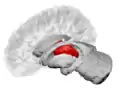

![]() The thalamus in a 360° rotation | |

The thalamus (pl.: thalami; from Greek θάλαμος, "chamber")[1] is a large mass of gray matter located in the dorsal part of the diencephalon (a division of the forebrain). Nerve fibers project out of the thalamus to the cerebral cortex in all directions, known as the thalamocortical radiations, allowing hub-like exchanges of information. It has several functions, such as the relaying of sensory signals, including motor signals to the cerebral cortex[2][3] and the regulation of consciousness, sleep, and alertness.[4]

The thalamus is a paired structure of gray matter about four centimetres long, located in the forebrain which is superior to the midbrain, near the center of the brain with nerve fibers projecting out to the cerebral cortex in all directions. The medial surface of the thalamus constitutes the upper part of the lateral wall of the third ventricle, and is connected to the corresponding surface of the opposite thalamus by a flattened gray band, the interthalamic adhesion. The lateral part of the thalamus is the phylogenetically newest part of the thalamus (neothalamus), and includes the lateral nuclei, the pulvinar and the medial and lateral geniculate nuclei.[6][7] There are areas of white matter in the thalamus including the stratum zonale that covers the dorsal surface and the external and internal medullary laminae. The external lamina covers the lateral surface and the internal lamina divides the nuclei into anterior, medial, and lateral groups.[8]